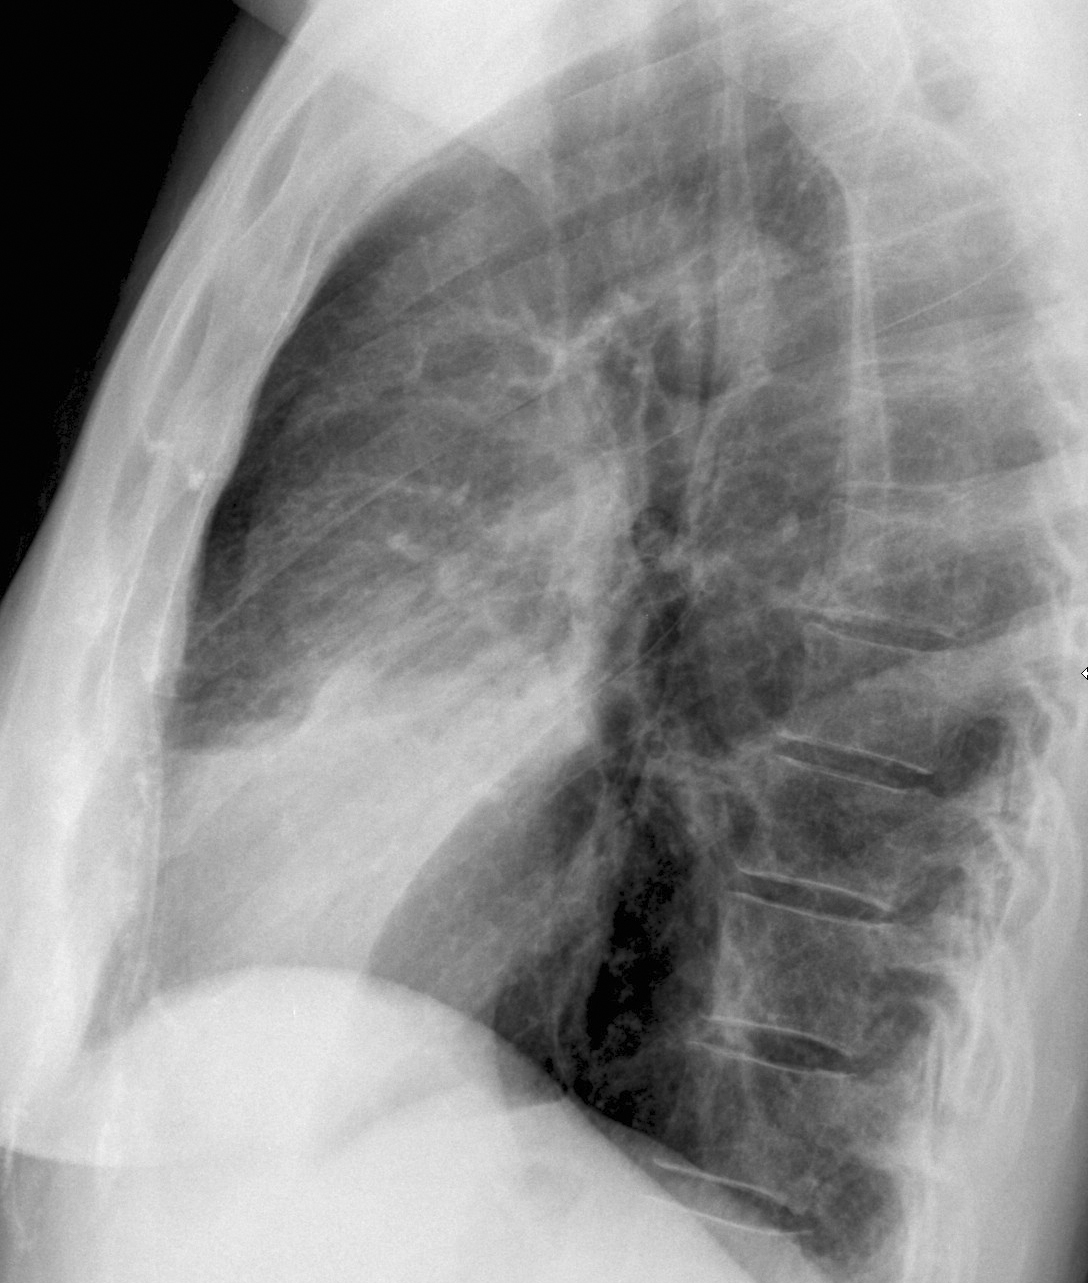

Lingular pneumonia Lat